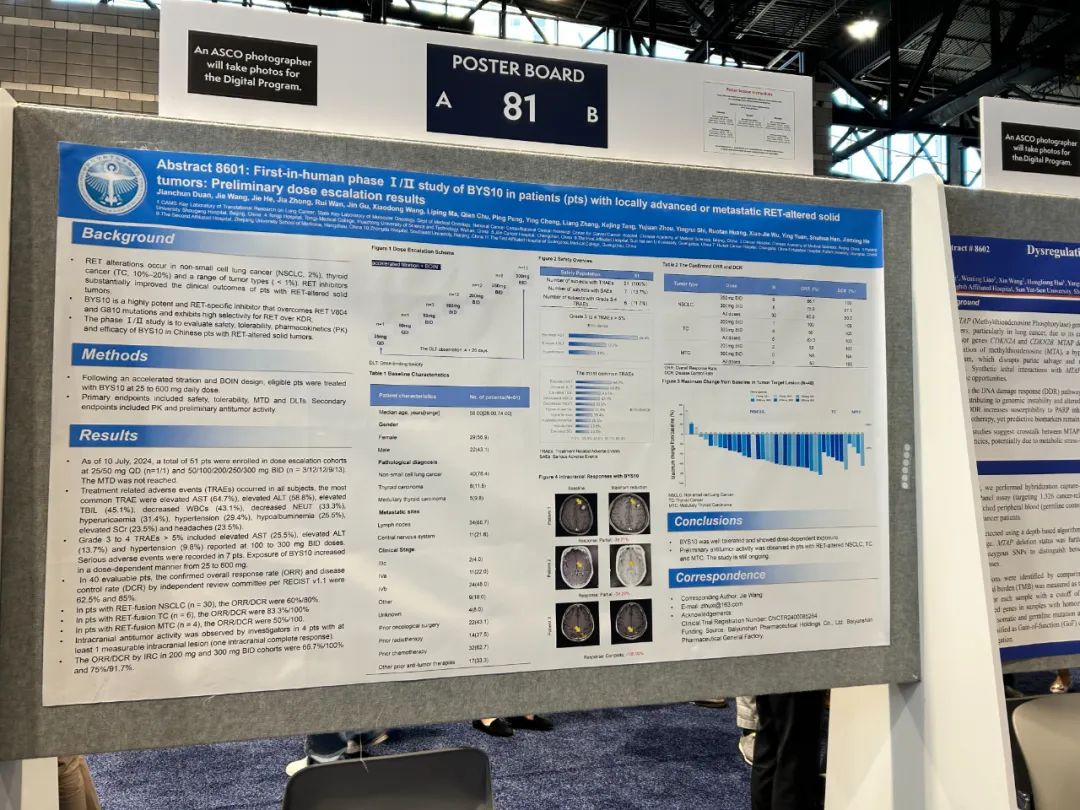

жИ™иЗ≥2024еєі7жЬИ10жЧ•�����пЉМ2дЊЛжВ£иАЕеИЂз¶їеЬ®еЙВйЗПйАТеҐЮйШЯеИЧдЄ≠жО•еПЧ25mg/QDеТМ50mg/QDеЙВйЗПеМїж≤ї�����пЉМеЕґдљЩ49дЊЛжВ£иАЕеИЂз¶їжО•еПЧ50mg/BIDпЉИn=3пЉЙгАБ100mg/BIDпЉИn=12пЉЙгАБ200mg/BIDпЉИn=12пЉЙгАБ250mg/BIDпЉИn=9пЉЙгАБ300mg/BIDпЉИn=13пЉЙеМїж≤ї[1]����гАВ